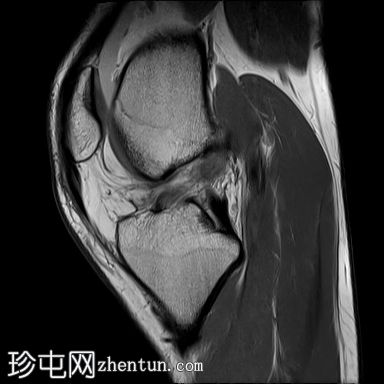

矢状位

PD脂肪抑制序列

前交叉韧带(ACL)完全断裂,PDFS和T2加权像显示韧带中部纤维信号增高,残余纤维下垂于胫骨平台,冠状位可见空切迹征。

此外,胫骨平台后外侧和股骨髁前外侧可见骨挫伤异常信号。

膝关节积液,主要位于髌上囊。